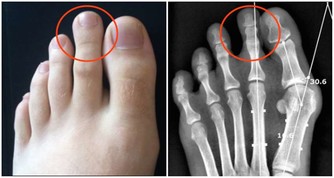

2.腸化生:有小腸型與大腸型兩種,小腸型(完全型)具有小腸黏膜的特徵,分化較好。大腸型(不完全型)與大腸黏膜相似,又可分為2個亞型:Ⅱa型,能分泌非硫酸化黏蛋白;Ⅱb型能分泌硫酸化黏蛋白,此型與胃癌發生關係密切。